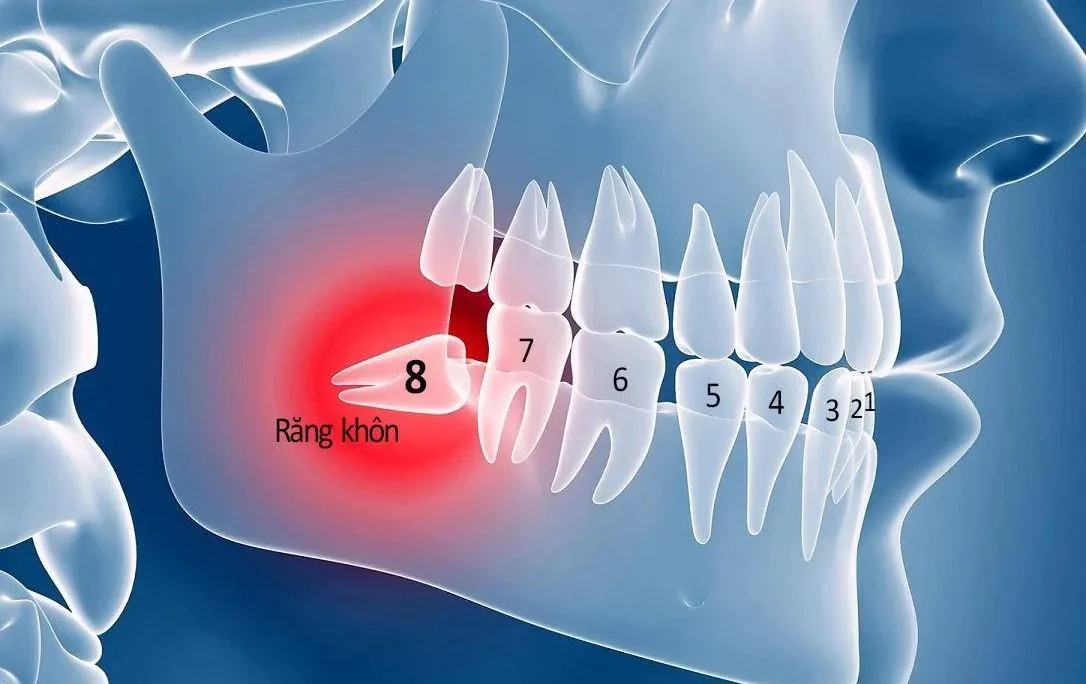

Trước khi tìm hiểu răng lấy tủy bọc sứ được bao lâu thì cần biết tủy răng là gì. Tủy răng là bộ phận nằm sâu bên trong thân răng. Nó bao gồm dây thần kinh và mạch máu có chức năng nuôi dưỡng và duy trì sự sống cho răng. Trong quá trình ăn nhai hằng ngày, một số người bệnh không chú trọng vệ sinh răng miệng đúng cách. Lúc này vi khuẩn và mảng bám có thể dễ dàng xâm nhập qua men răng và ngà răng. Từ đó tấn công vào buồng tủy.

Việc không kiểm soát tốt răng miệng có thể dẫn đến nhiều bệnh lý nguy hiểm. Ví dụ như viêm tủy răng, áp xe quanh chóp răng, sâu răng lan rộng. Khi mắc phải chúng sẽ gây ra cảm giác đau nhức dữ dội, ê buốt kéo dài. Từ đóảnh hưởng nghiêm trọng đến sinh hoạt hàng ngày và chất lượng cuộc sống. Trong nhiều trường hợp, nếu không điều trị kịp thời, tủy răng bị hoại tử. Khi đó có thể buộc phải lấy bỏ tủy răng, thậm chí dẫn đến mất răng vĩnh viễn.

Do đó, bạn nên chủ động đến cơ sở nha khoa uy tín. Thông qua đó được kiểm tra và điều trị kịp thời những vấn đề răng miệng. Việc can thiệp sớm không những giúp bảo tồn tủy răng tự nhiên. Nó còn hạn chế nguy cơ biến chứng. Thông qua đó tiết kiệm chi phí điều trị lâu dài và duy trì sức khỏe răng miệng toàn diện.